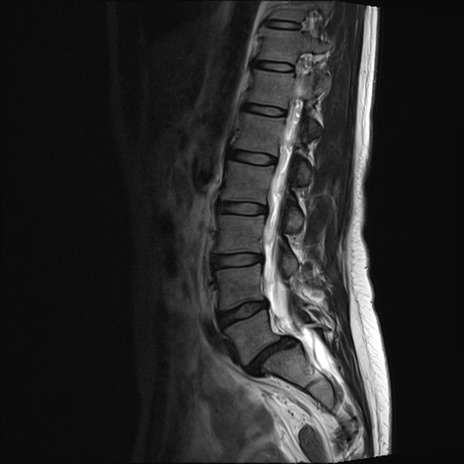

【整形】TIPS症例4 腰椎MRI T2WI(矢状断像)

腰椎MRI

T1WI(矢状断像)